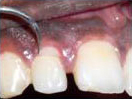

Labial Soft Tissue

Reflected

Tooth with Fracture Extending Sub-Gingivally

Palatal Soft Tissue